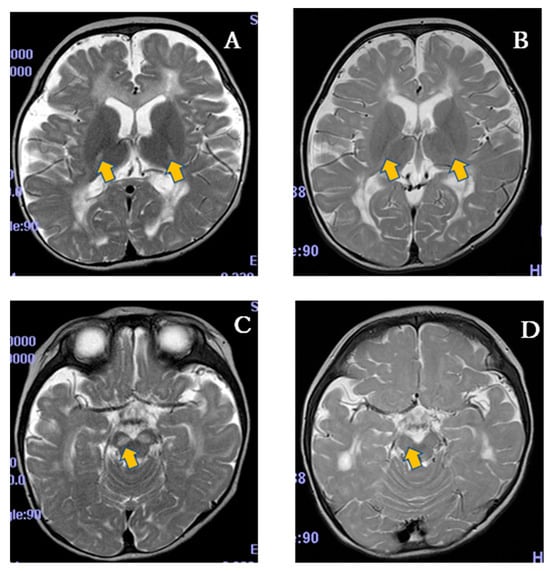

| MRI abnormality | Basal ganglia lesion MRS lactate peak | Basal ganglia lesion | Basal ganglia lesion | Basal ganglia lesion | Basal ganglia lesion | Basal ganglia lesion | Basal ganglia lesion | Basal ganglia lesion | Basal ganglia lesion | Basal ganglia lesion |